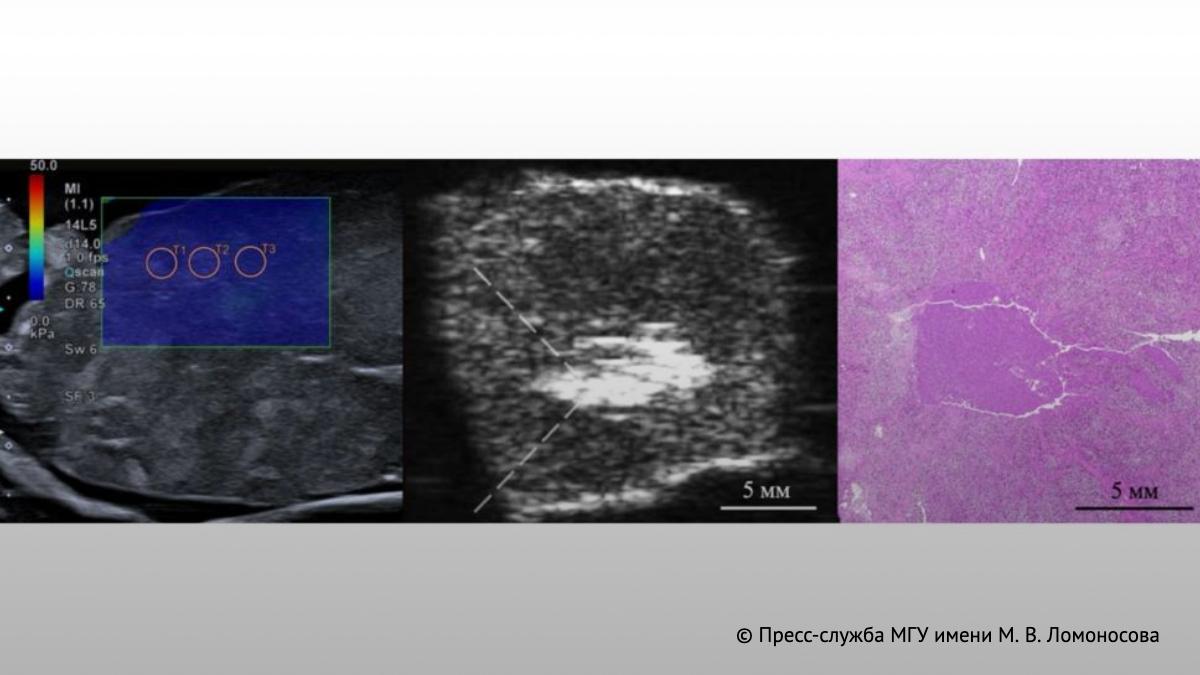

Идея метода проста: фокусированная серия высокоамплитудных ультразвуковых импульсов миллисекундной длительности проходит через кожу и здоровые ткани и воздействует прямо на опухоль. Разрушение происходит не за счёт нагрева, а механически, через ударные фронты акустических волн. Здоровые ткани при этом остаются неповреждёнными. Гистологический анализ показал: опухолевые клетки полностью разрушаются, при этом граница между повреждённой и здоровой тканью не превышала 200 микрометров.